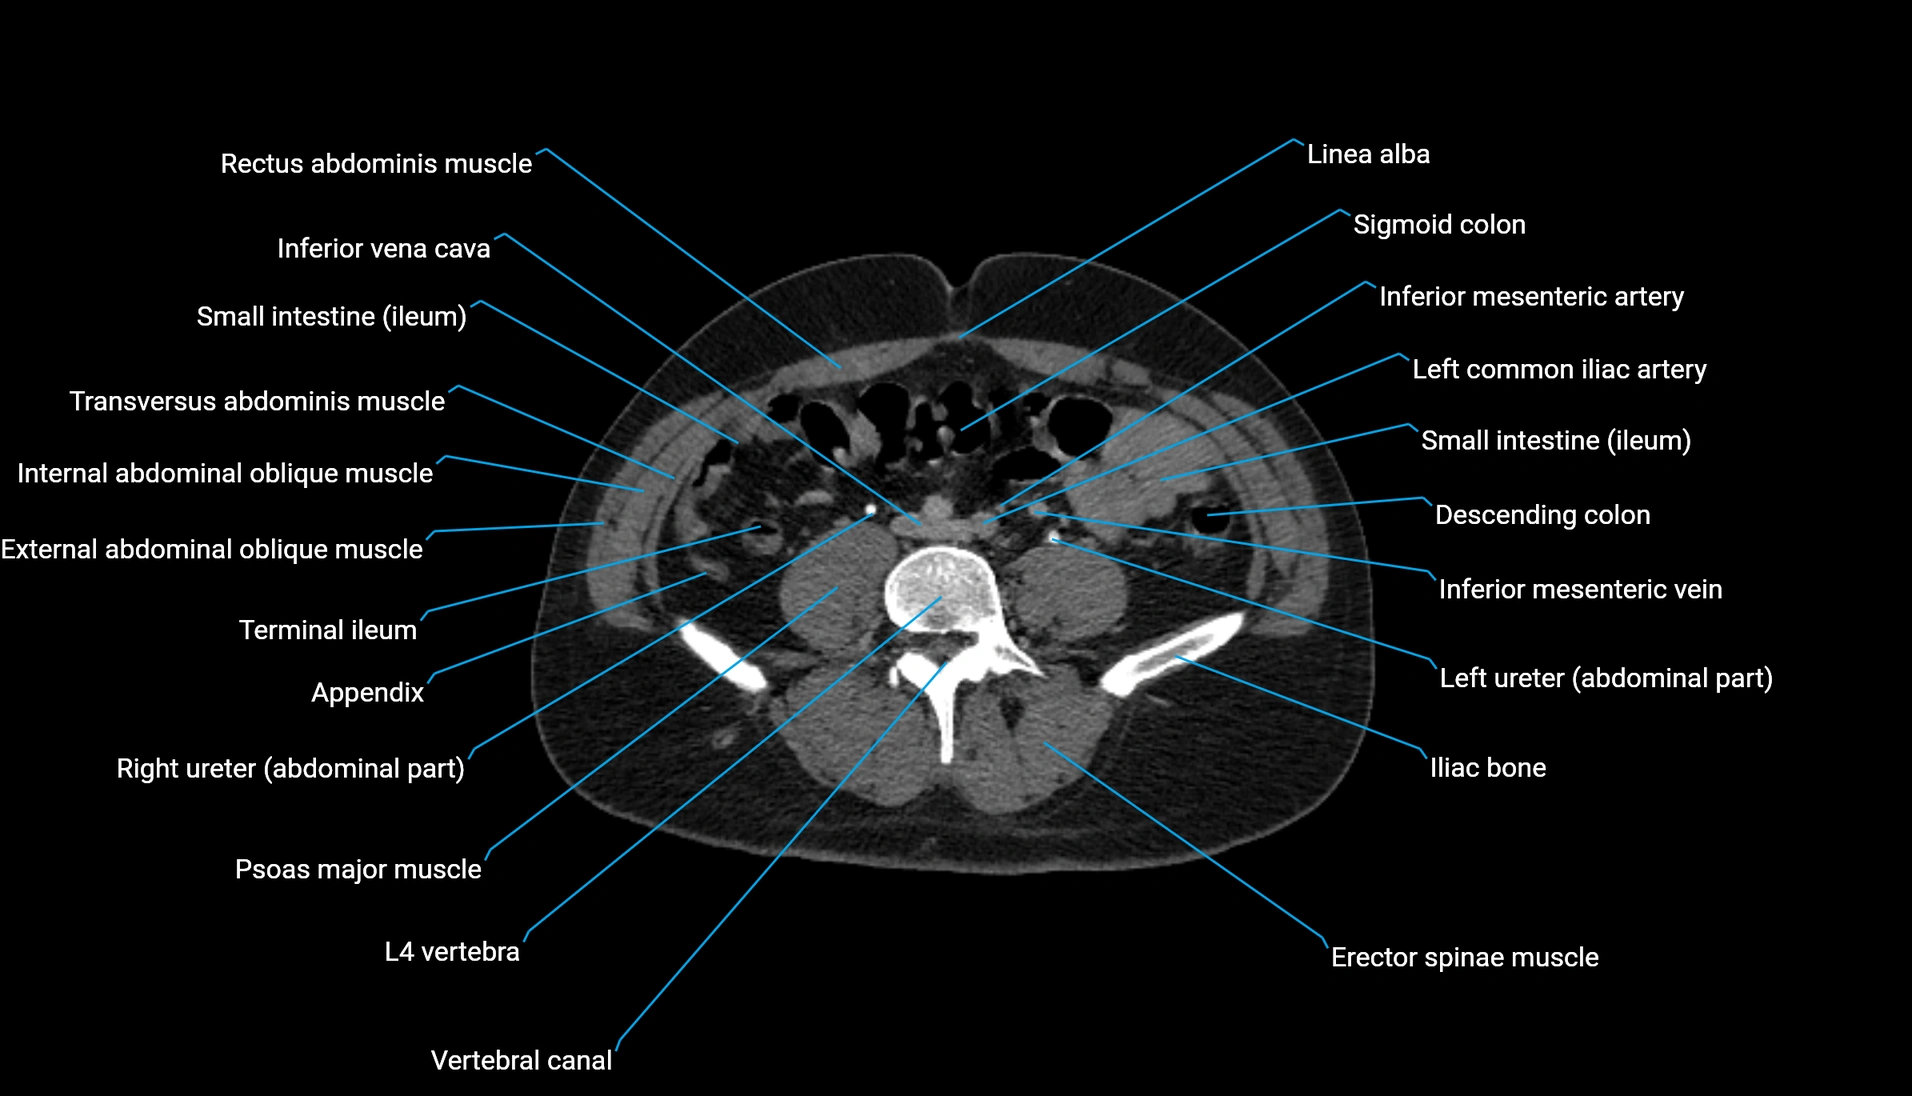

CT Appearance

Non-contrast CT:

-

Demonstrates cortical bone of acetabular rim in excellent detail

Detects fractures, dysplasia, retroversion, or bony overcoverage (pincer impingement)

3D reconstructions used in preoperative hip surgery planning

CT image